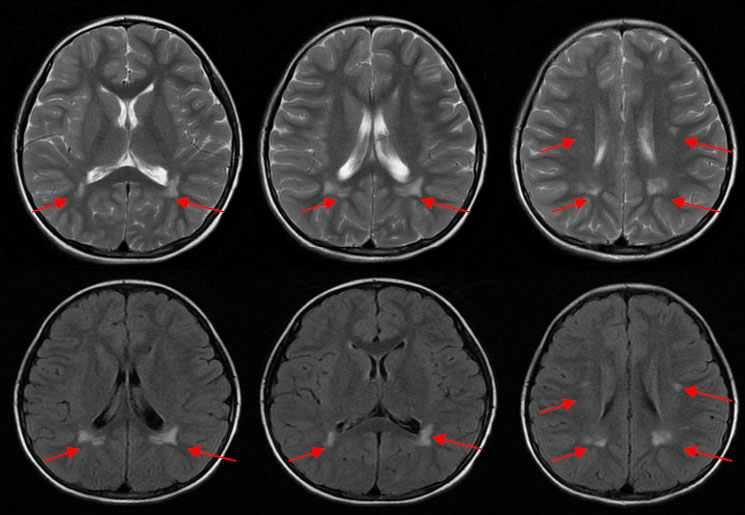

MRI表现为侧脑室旁对称性的异常信号灶,增强后可见斑点状轻度强化。

1)弥漫型:大脑半球、基底节区、丘脑及小脑半球实质内斑片状、斑点状等或长T1、长T2信号灶,周围可见水肿或无明显水肿,病变可累及灰白质。增强后呈斑片状、斑点状、脑回状轻-中度强化。

2)局灶型:单发局限性上述信号灶。